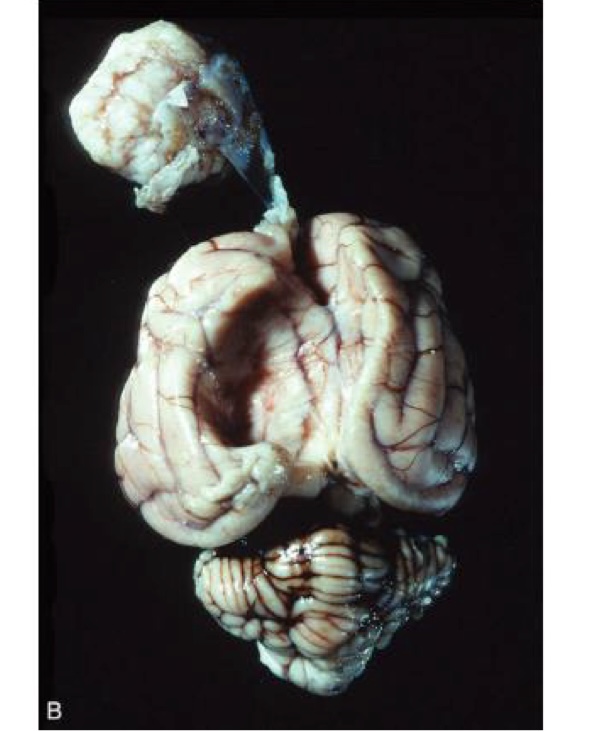

what is this?

medulloblastoma → white to tan, homogenous mass that compresses the cerebellum and brainstem